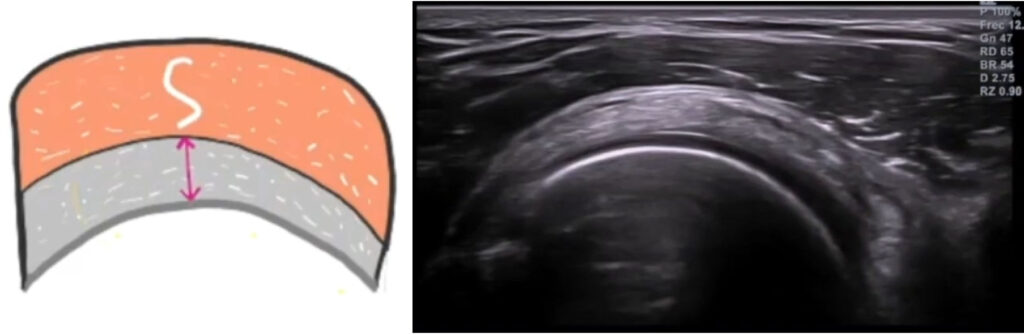

En este corte, podrás ver el músculo deltoides en una interfase más superficial, seguido de la bursa (inapreciable en condiciones normales, se ve como una delgada capa anecoica entre el vientre muscular y el tendón). Después, está el tendón del supraespinoso, que tiene forma de pico de loro. Por debajo encontraremos el cartílago articular completamente hipoecoico y la cortical de la cabeza humeral.

La imagen no patológica, corresponderá a la siguiente (bursa señalada en azul):